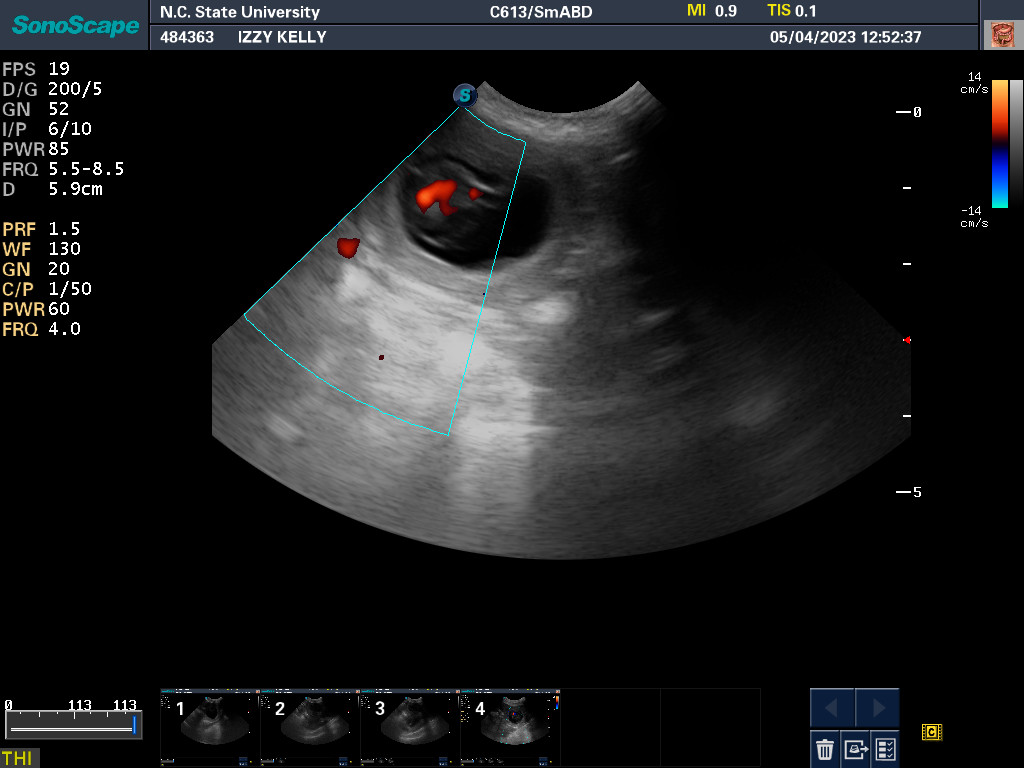

NC State University for an autopsy.